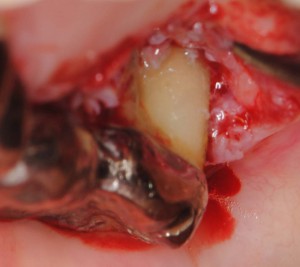

歯石をとって、この後歯肉を戻して縫合

歯石をとって、この後歯肉を戻して縫合